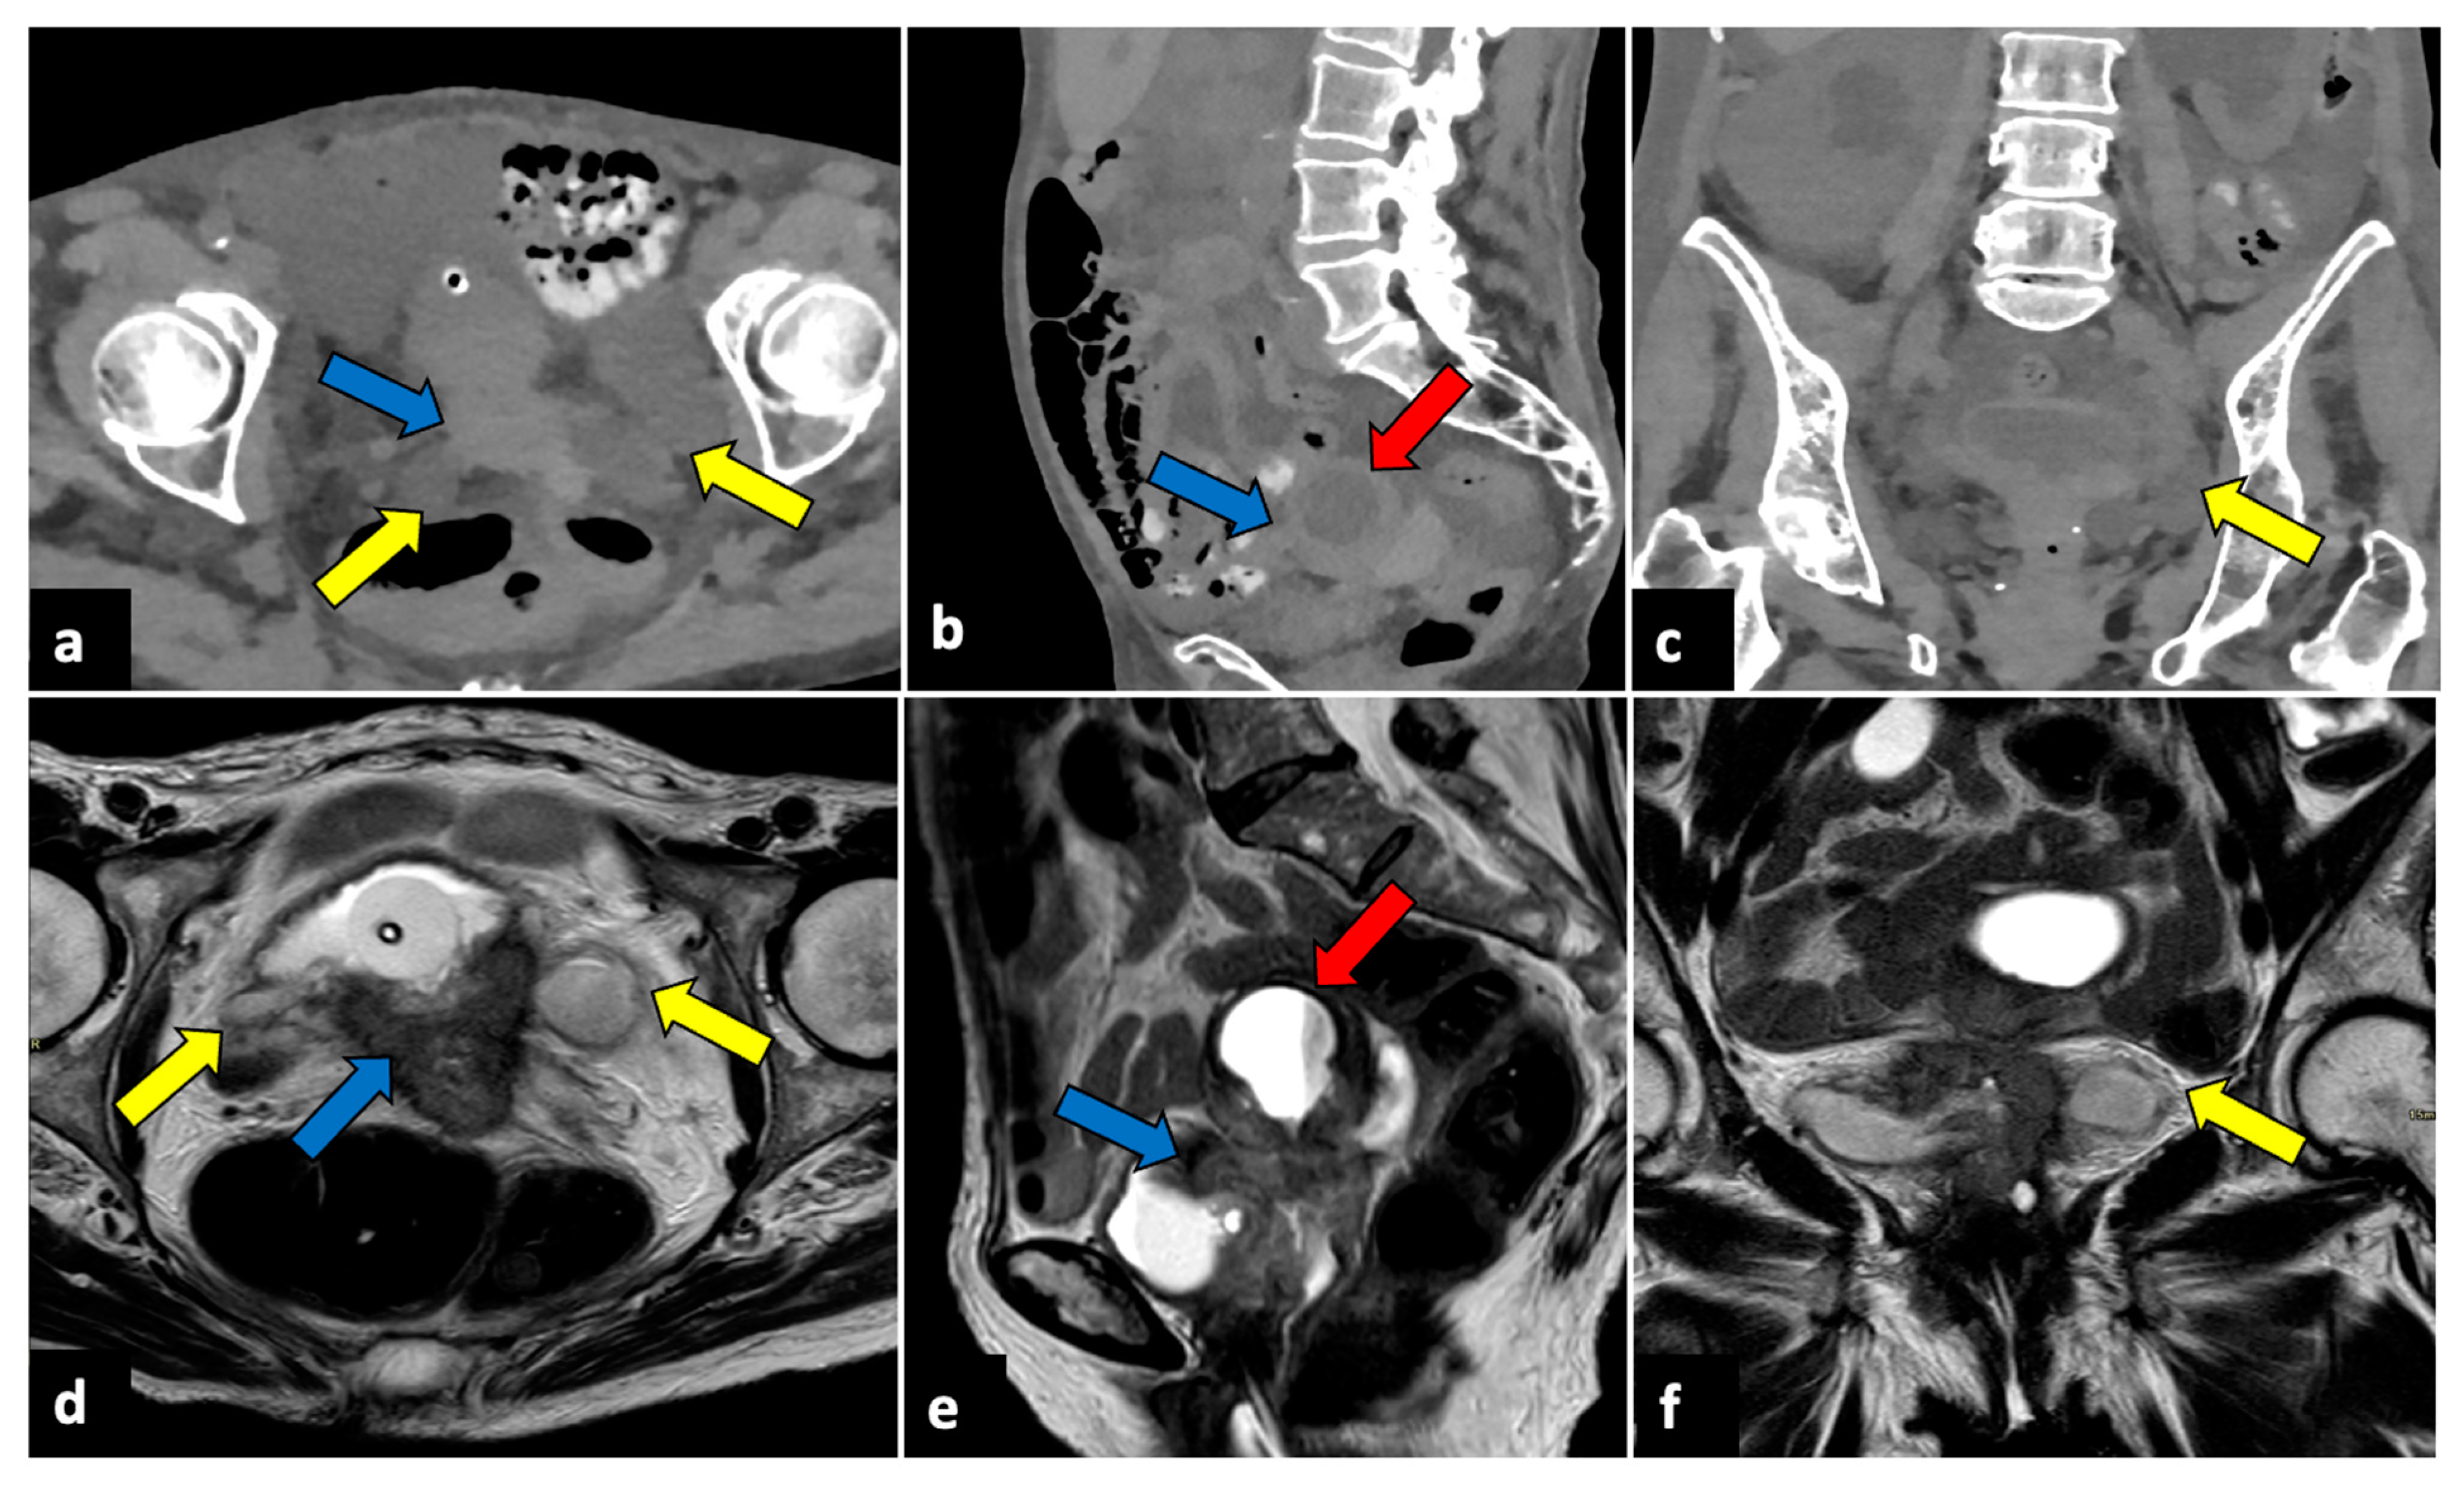

Pelvic malignancies, most commonly ovarian, cervical, and endometrial uterine cancers, can induce pain of different intensities and durations. Gynaecological cancer may present with sudden onset in cases of advanced stages, with the invasion of adjacent structures that lead to several complications, such as intestinal perforation, thrombosis, and intestinal or ureteral obstruction (Figure 10) [71,72,73].

Figure 10.

Advanced uterine cervical cancer in a 58-year-old subject attending the emergency department for abdominal pain and haematuria. CT axial (a), sagittal (b), and coronal (c) non-contrast images reveal the presence of a pelvic mass (blue arrows) and ureter causing ureteral obstruction (yellow arrows). The patient further underwent an MRI examination (d–f), which demonstrated a cervical tumour (blue arrows) invading the parametrium and ureters bilaterally (yellow arrows), the vagina, and the bladder. The uterine cavity was also obstructed and dilatated (red arrows).